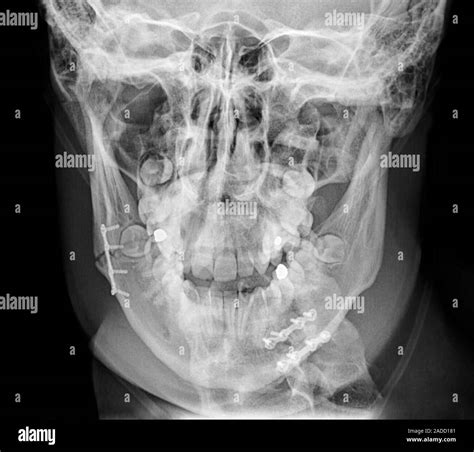

• X-Rays: X-rays are commonly used to visualize the bone and identify fractures.

• CT Scans: In more complex cases, a CT scan may be ordered to provide a detailed view of the jaw and surrounding structures.

• Immobilization: The jaw may be immobilized using wires, elastic bands, or other devices to keep the teeth aligned and promote healing.

• Surgery: In severe cases, surgery may be required to realign the bone fragments and stabilize the jaw. This may involve the use of plates, screws, or other hardware.